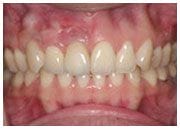

治療前

陳小姐在本診所經過矯正治療後,想要讓排列整齊的牙齒更漂亮,於是將舊有不美觀的假牙換掉,以更優質的全瓷冠人工植牙重建,同事們都說她簡直像變了一個人,不但有漂亮的瓜子臉,牙齒更是自然漂亮,完全看不出來有做過假牙,這就是全瓷冠植牙的魔力。